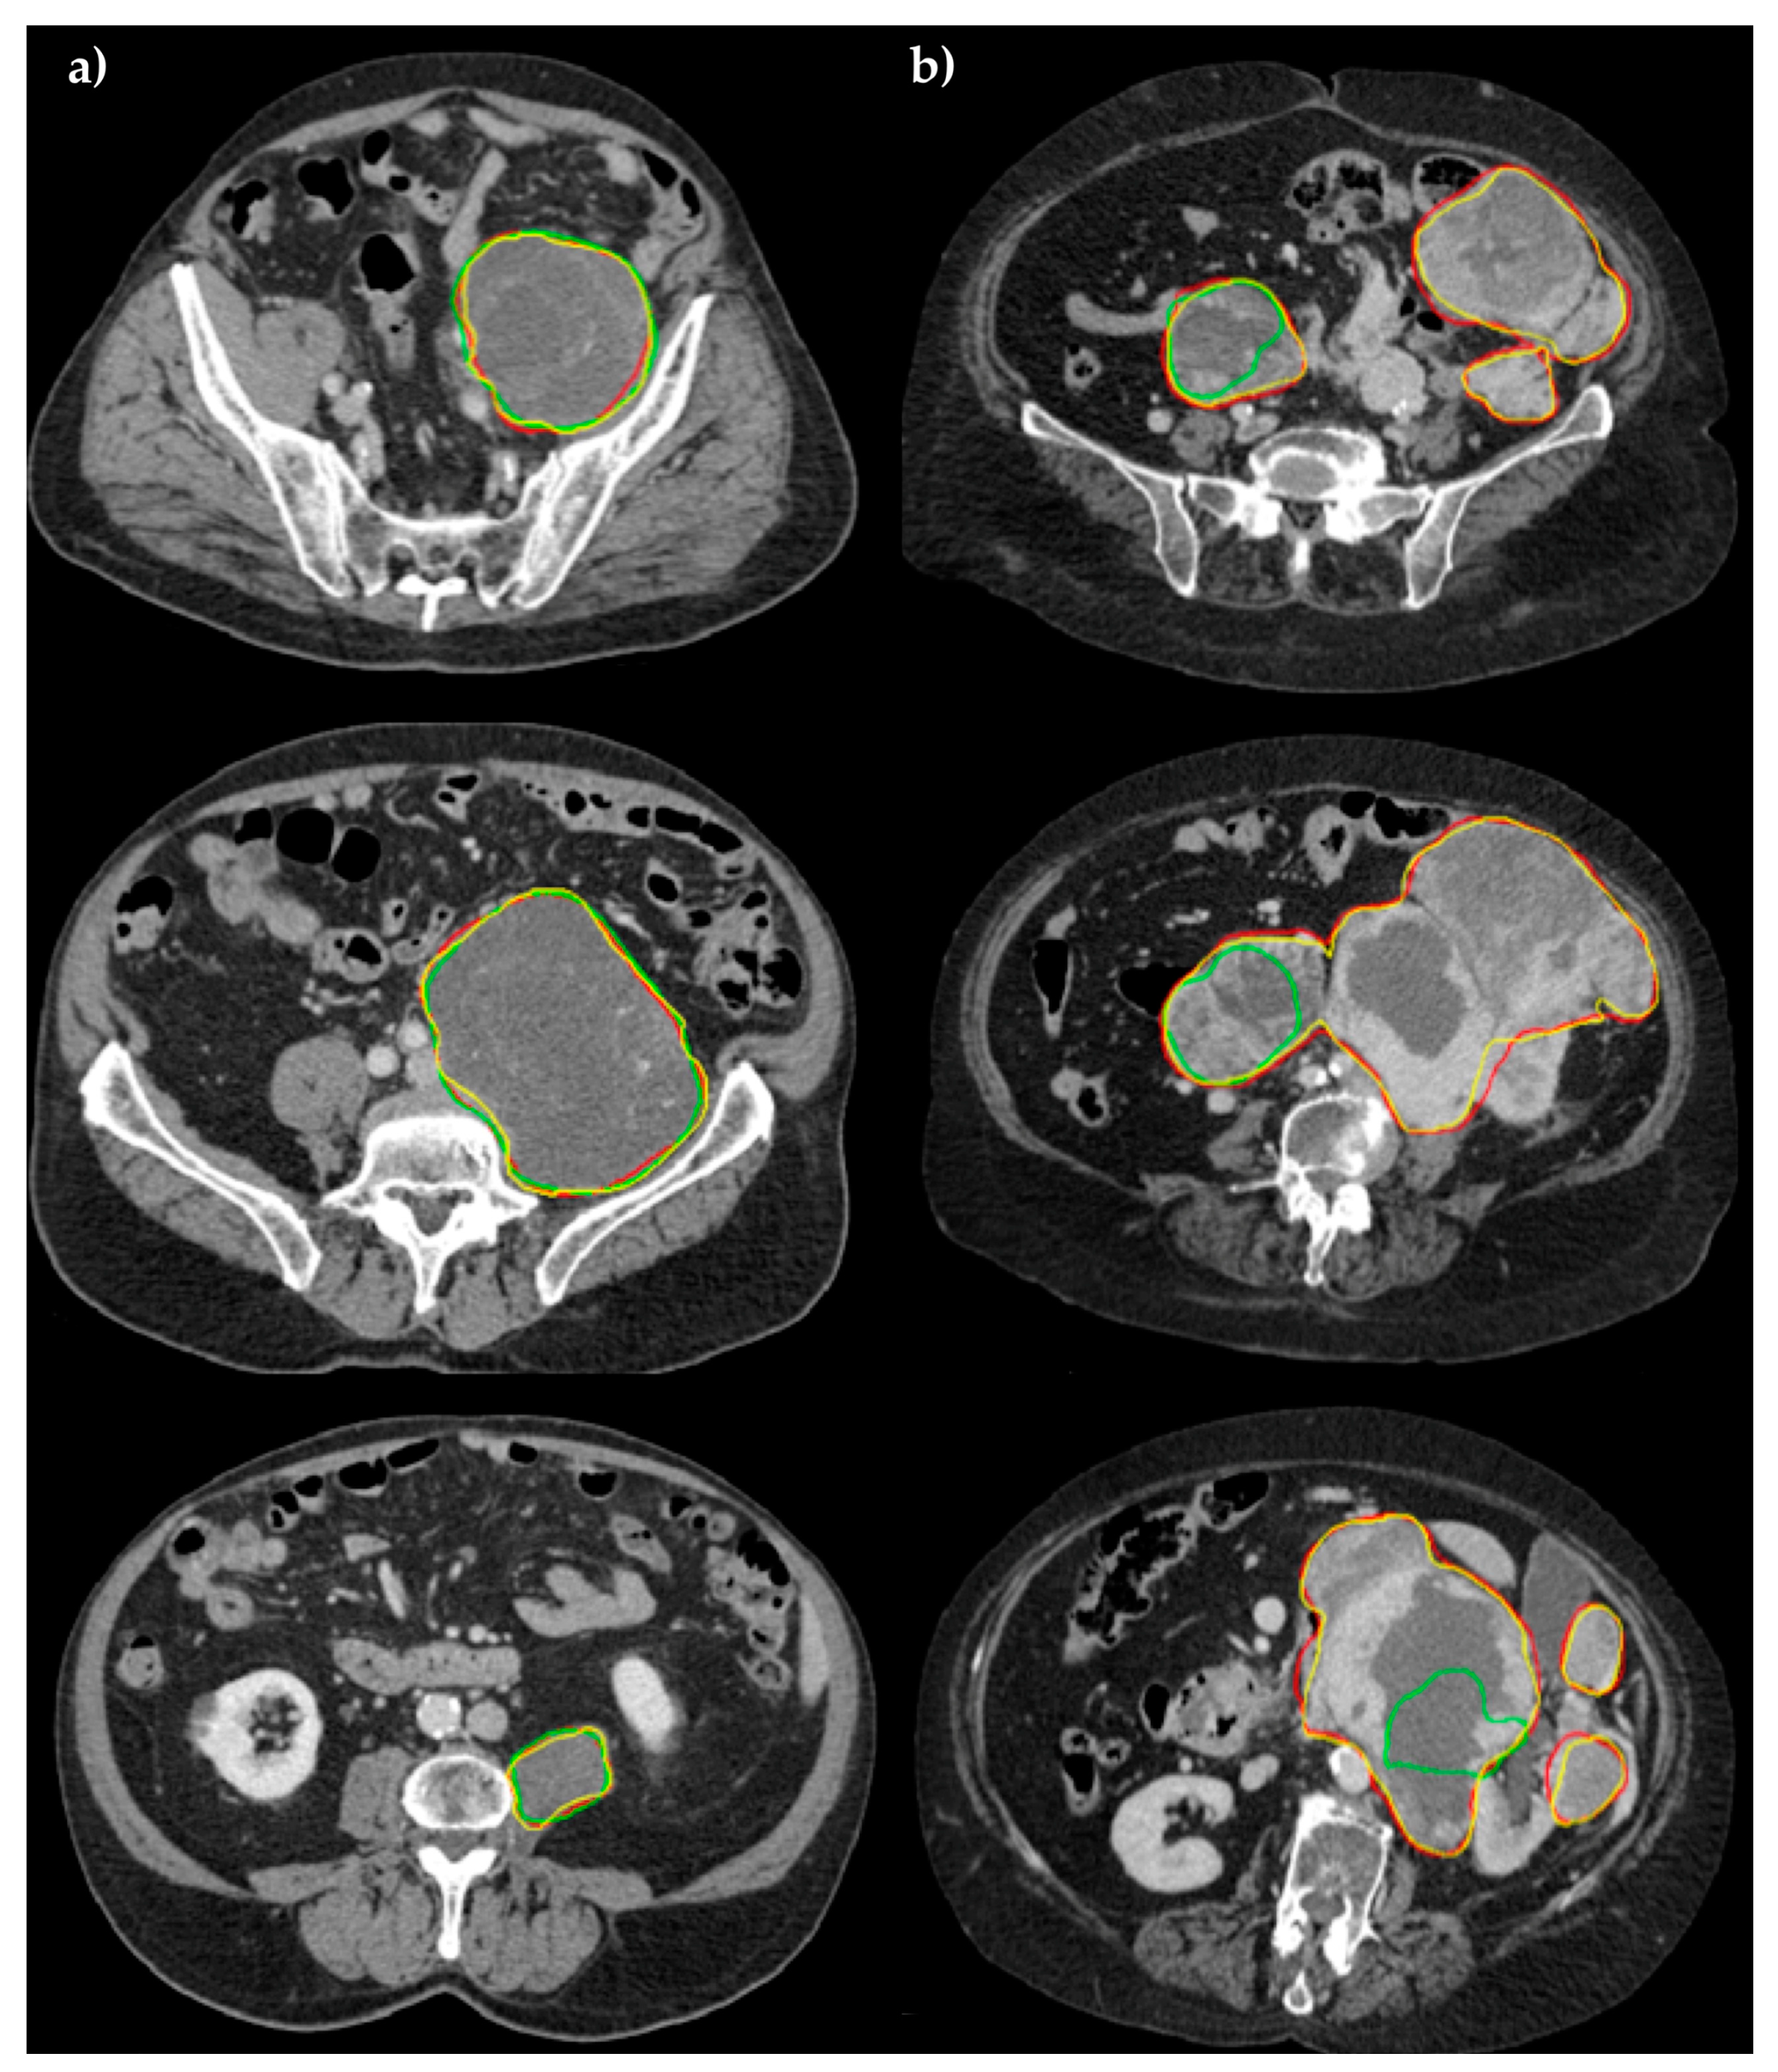

| Sensitivity | PPV | DSC | VOE | VD | |

|---|---|---|---|---|---|

| ENet | |||||

| Mean ± SD | 91.54 ± 7.49% | 89.85 ± 5.66% | 90.52 ± 5.49% | 16.87 ± 8.81% | 2.11 ± 8.53% |

| ±CI (95%) | 4.89% | 3.70% | 3.59% | 5.76% | 5.58% |

| ERFNet | |||||

| Mean ± SD | 72.21 ± 26.11% | 87.00 ± 8.00% | 74.85 ± 19.28% | 36.85 ± 21.87% | −14.80 ± 33.32% |

| ±CI (95%) | 17.06% | 5.23% | 12.60% | 14.29% | 21.77% |